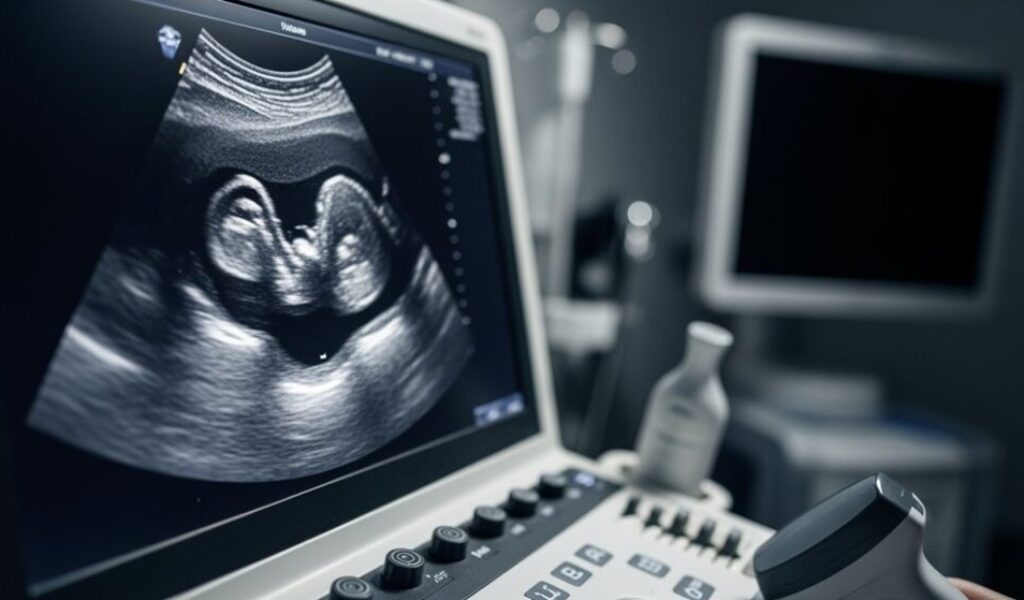

Ultraschall ist ein bildgebendes Verfahren, das ohne Strahlenbelastung auskommt und deshalb in Schwangerschaft und Geburtshilfe besonders häufig eingesetzt wird. Ein handlicher Schallkopf sendet hochfrequente Schallwellen in den Körper; das Gerät fängt die Echos auf und formt daraus bewegte Bilder in Echtzeit. So lassen sich Organe, Gefäße und – in der Schwangerschaft – das werdende Baby schonend beurteilen. Die Methode gilt als sicher, nichtinvasiv und vielseitig und begleitet Familien vom ersten Schwangerschaftstest bis in die Wochenbettversorgung.

Beim Ultraschall entstehen Bilder nicht durch Röntgenstrahlen, sondern durch Schall. Der Schallkopf berührt die Haut, ein Gel sorgt für guten Kontakt, und kurze Schallimpulse breiten sich im Gewebe aus. Trifft eine Welle auf eine Grenze – etwa zwischen Muskel und Flüssigkeit – wird ein Teil zurückgeworfen. Aus der Zeit, die das Echo braucht, und aus seiner Stärke berechnet das Gerät Lage und Beschaffenheit der Struktur. Dichte Grenzflächen erscheinen hell, flüssigkeitsgefüllte Bereiche dunkel; das Bild entsteht fortlaufend und zeigt Bewegungen wie Herzschlag oder Blutfluss. Mit wenigen Reglern lässt sich die Darstellung anpassen: Tiefe, Helligkeit, Fokus und – je nach Fragestellung – die Frequenz des Schallkopfs. Höhere Frequenzen liefern feine Details in geringer Tiefe, niedrigere dringen weiter in den Körper ein. Ein spezieller Modus, der sogenannte Doppler, macht Bewegung sichtbar: Er erkennt kleine Frequenzverschiebungen der Echos und kann so Flussrichtung und -geschwindigkeit des Blutes farbig über das Bild legen.

Ultraschall strukturiert die gesamte pränatale Betreuung. Früh in der Schwangerschaft bestätigt er Lage und Vitalität, hilft beim Datieren der Schwangerschaft und erkennt Mehrlinge. Im ersten Trimester kann die Nackentransparenz gemessen und zusammen mit anderen Parametern das individuelle Risiko für bestimmte Chromosomenstörungen eingeschätzt werden. Der große Anatomiescan um die Schwangerschaftsmitte prüft Organe, Wirbelsäule, Extremitäten, Herz und Gehirnstrukturen. Später liefern Verlaufskontrollen Informationen zu Wachstum, Fruchtwassermenge und Lage des Kindes; auch die Plazenta wird beurteilt, etwa bei Verdacht auf Plazenta praevia. Bei Wachstumsauffälligkeiten oder anderen Risiken kommt der Doppler zum Einsatz, um den Widerstand in Nabelschnur- und kindlichen Gefäßen zu messen. Kurz vor der Geburt kann Ultraschall helfen, die Lage (Schädellage, Beckenendlage), das geschätzte Gewicht und die Plazentalokalisation zu klären und Entscheidungen zur Geburtsplanung zu unterstützen. Unter der Geburt wird Ultraschall punktuell genutzt, um die kindliche Position zu überprüfen oder Verfahren zu begleiten.